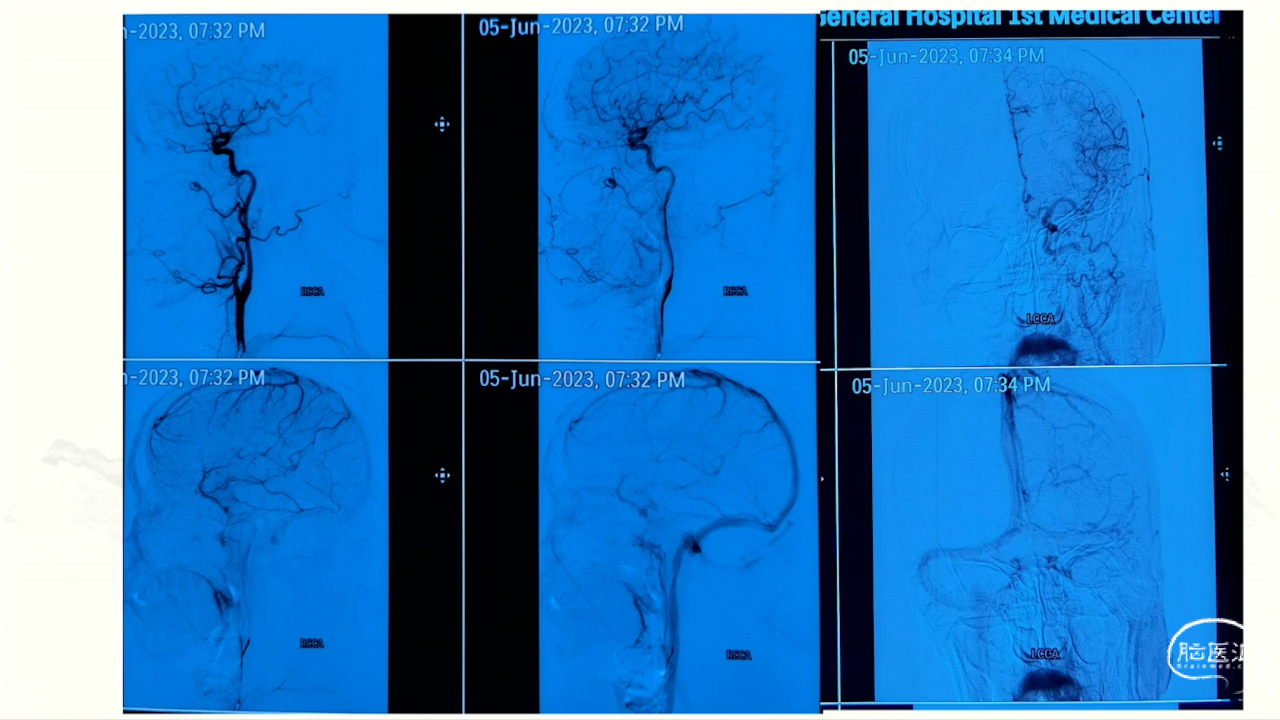

卜博教授:颈静脉孔区肿瘤:解剖及156例经验

颈静脉孔区肿瘤充分显露是硬道理。肿瘤越大,工作通道越宽。颈静脉孔扩大越明显,开放颈静脉孔越容易。